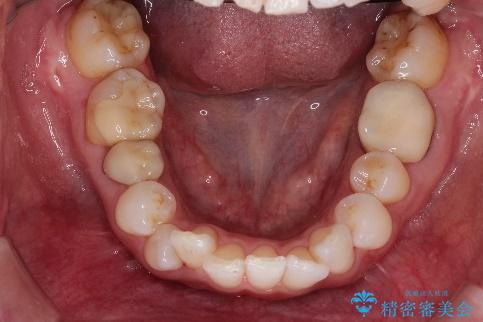

インビザラインによる非抜歯矯正 ガタガタな歯並びを整った歯並びへ

- 上下の全体的ながたつきが気になるとのことで来院されました。

全体的に歯と歯の間にわずかに隙間を作り、歯を並べました。